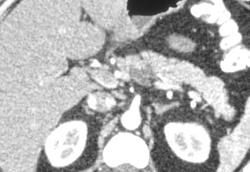

Pancreatitis Post-ERCP